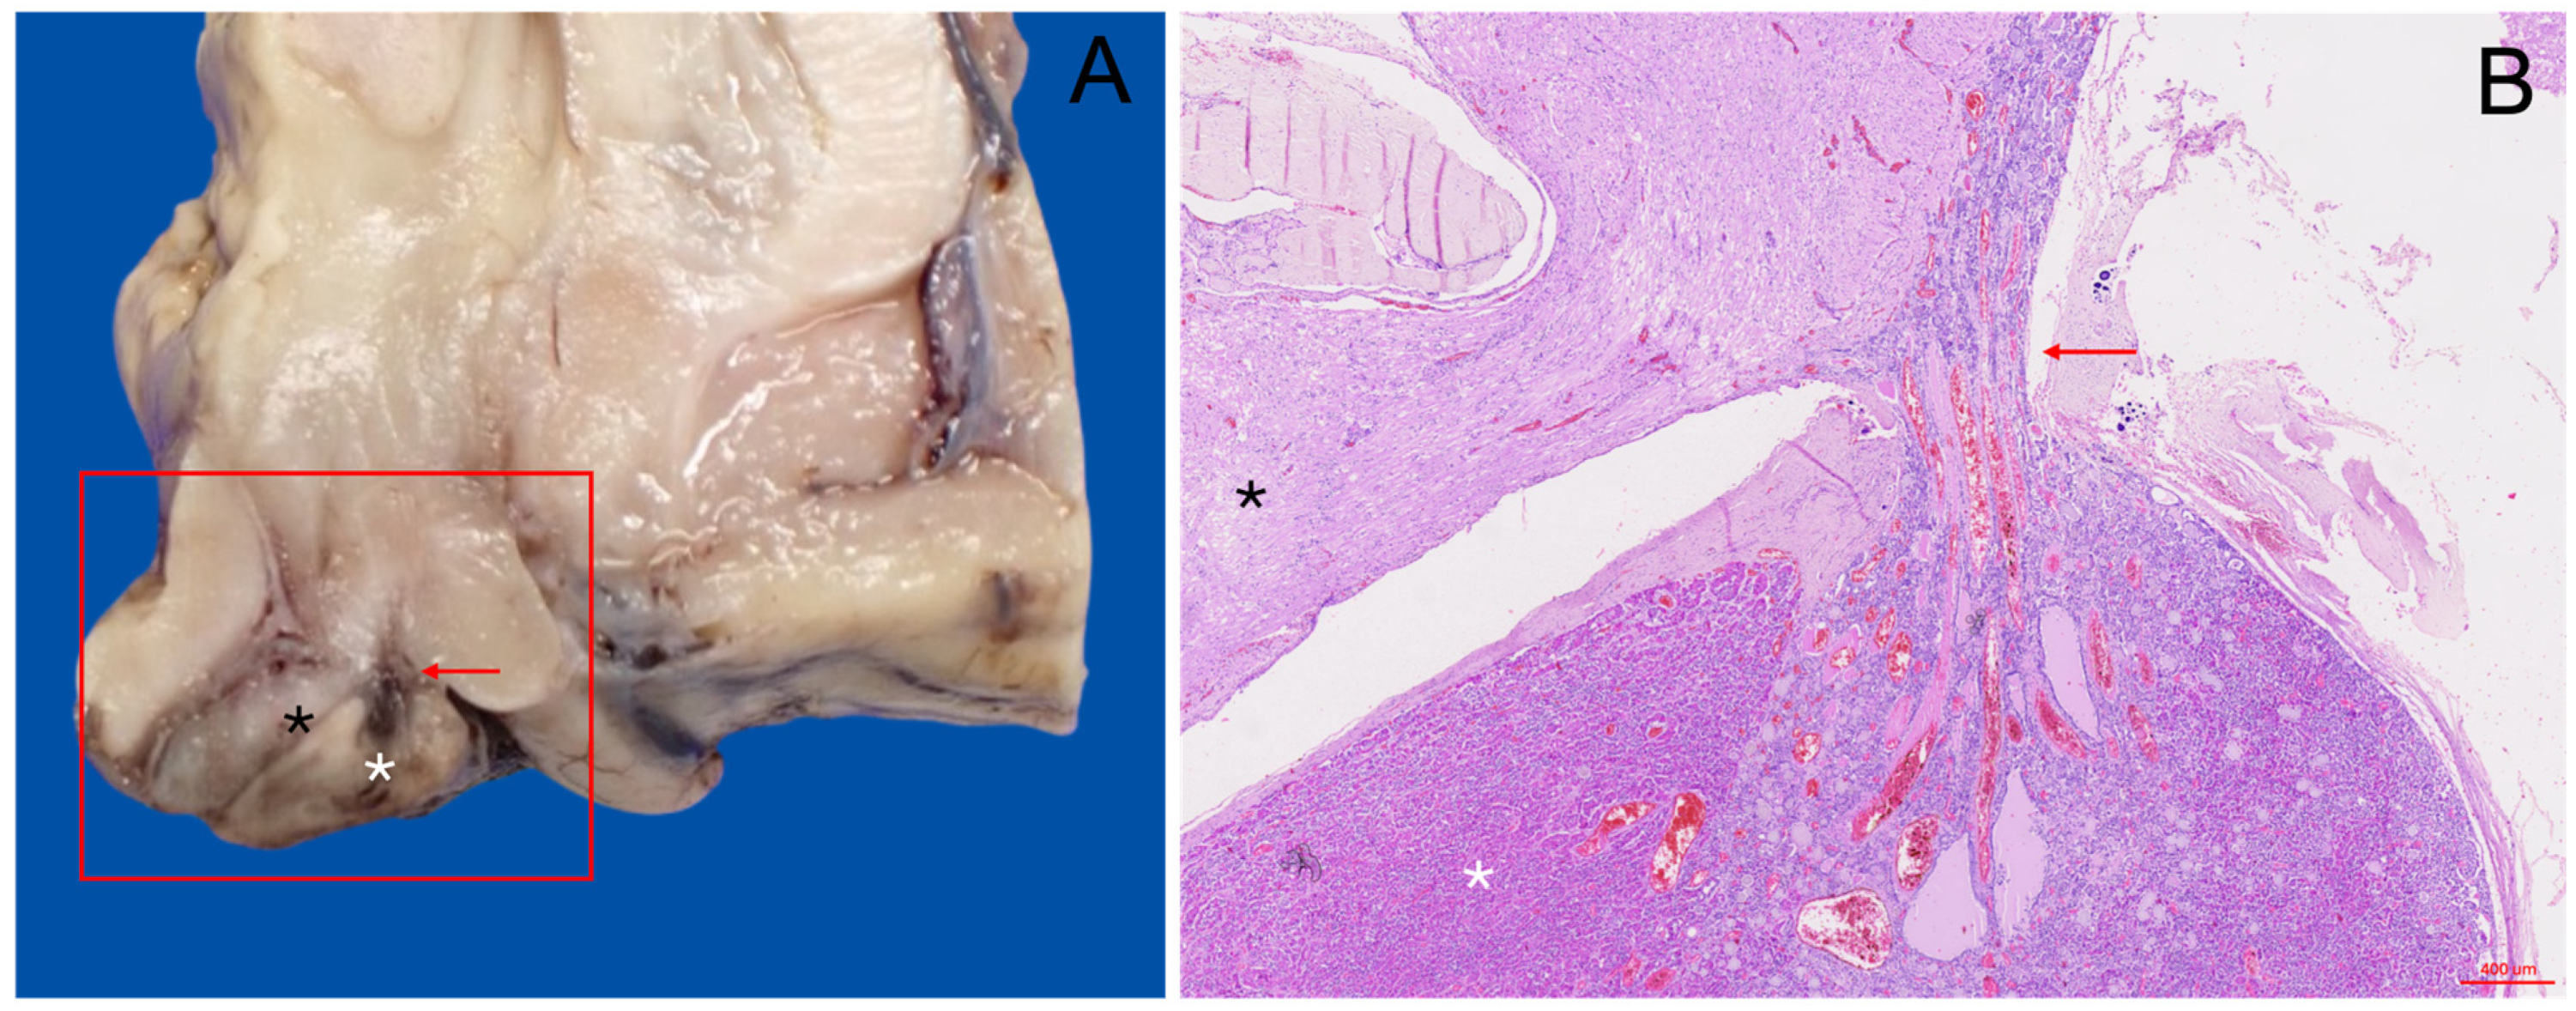

3.2. Gross Anatomical Description

3.3. Histological Description